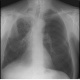

Здравствуйте, уважаемые колеги! Согласен с Андреем Юрьвичем. Состояние после правосторонней верхнедолевой лобэктомии. Средняя доля справа ушла вверх (природа не любит пустоты). Викарная эмфизема левого легкого. Спайки, фиброз, правосторонний фиброторакс. Но справа в проекции S6 полость с горизонтальным уровнем жидкости - хорошо видно на боковом. Может в междолевой щели осумкованный плеврит, абсцесс, эмпиема. Хотелось бы знать немного больше анамнеза, кроме операции. Боли, кашель, температура, изменения в анализе крови и т.д.

В проекции С6 уровень вижу, апикально нет. За абсцесс не вижу четкой нижней границы. Осумкованные междолевые не дают уровень. Ограниченную послеоперационную эмпиему не исключаю на фоне рассасывающегося геморрагического плеврита и фиброторакса...

Фиброз может давать весьма причудливую картину. Уровень жидкости надо доказывать. Хотя бы латерографией.

Два. Один на верхушке, второй в м/долевой щели. Обычная картина после операции. Если есть клиника воспаления, их пунктируют